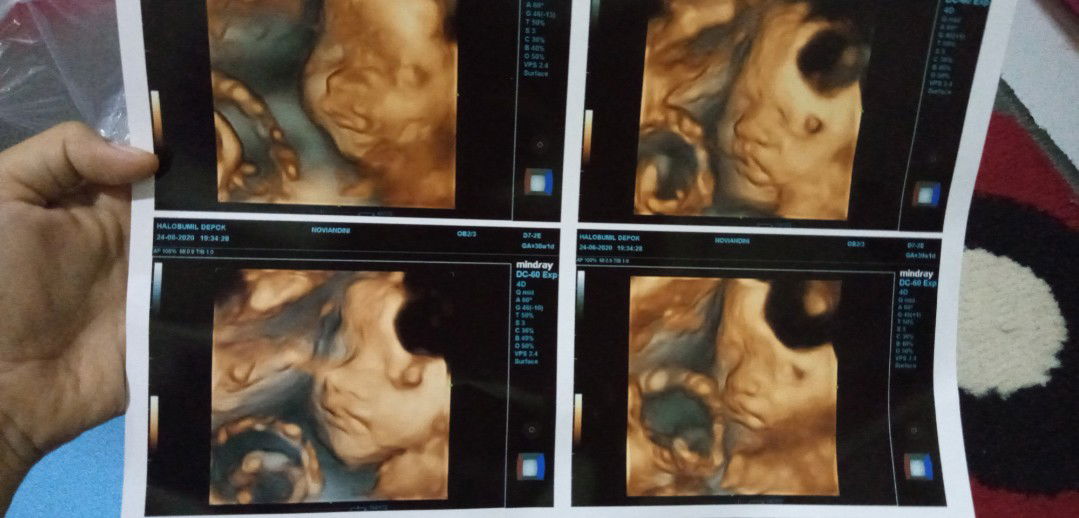

tentang usg 4d

Halo bunda2 syantik, aku abis USG 4D, aku perempuan bun😍 Btw bunda2 yg pernah usg 4d hasilnya gt juga gak? Aku msh kepikiran itu bentuk bibirnya kyk gt normal kan yah, bkn sumbing? Atau memang 4d hasilnya gt semua? Mohon bantuan utk responnya ya bun😉🤗